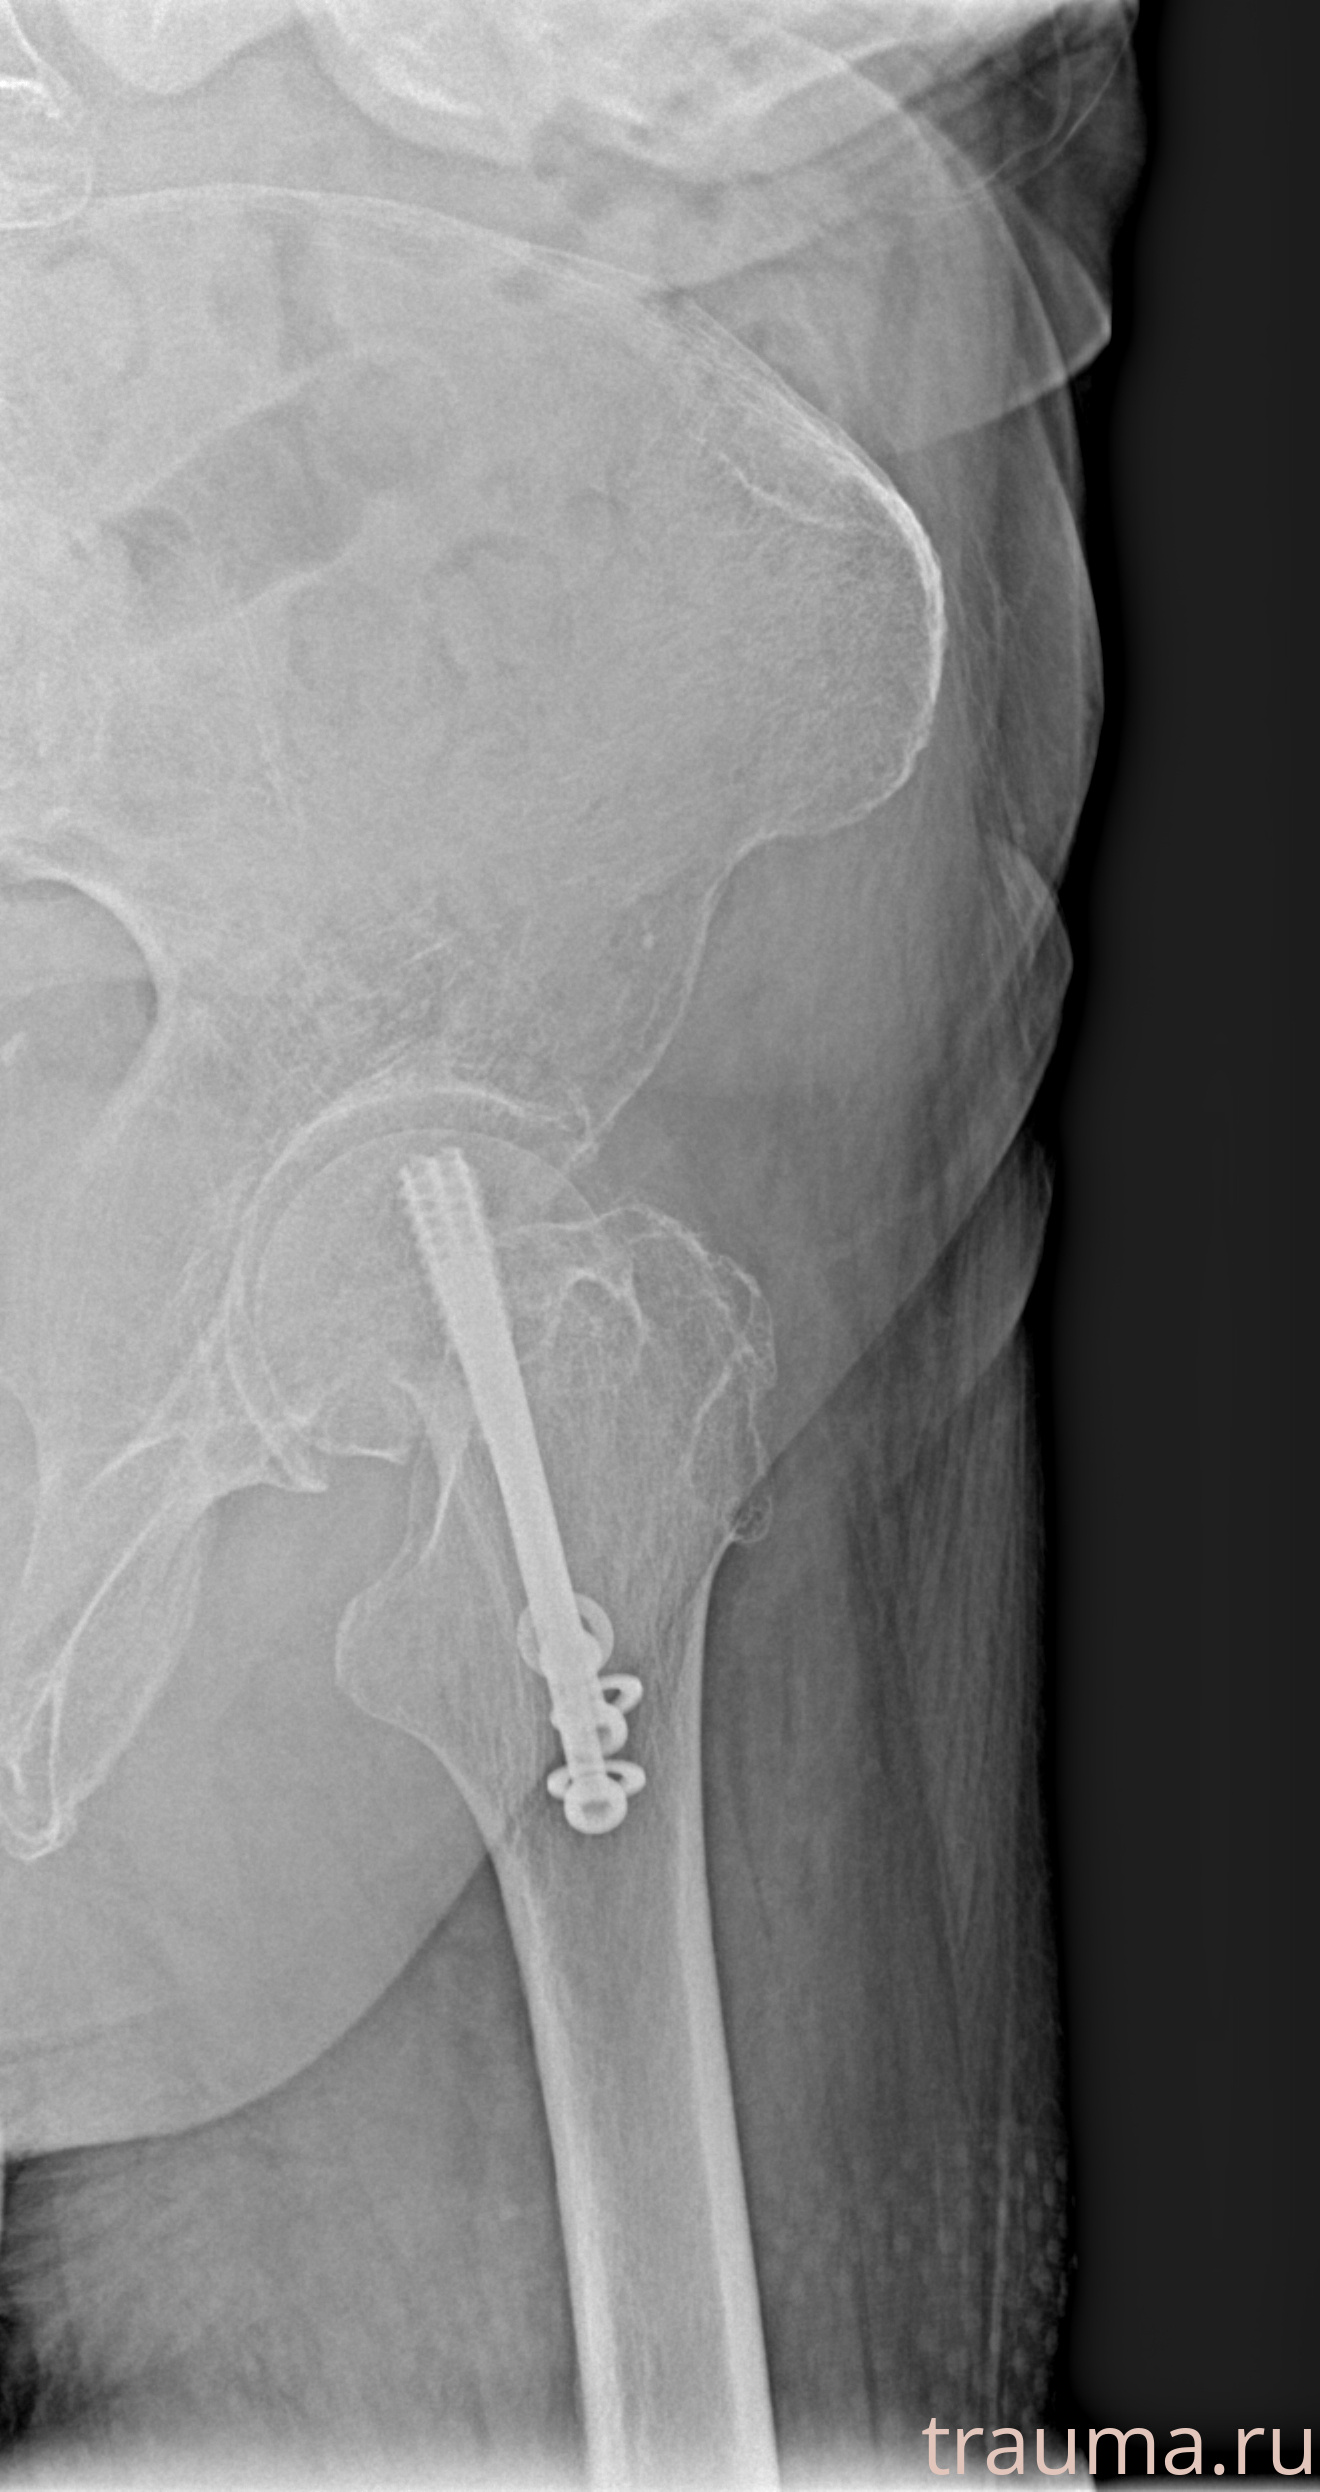

Рентген на дому: по вашему адресу приезжает врач-рентгенолог, травматолог-ортопед с мобильным рентгеновским аппаратом, проводит диагностику травмы или заболевания, делает необходимые рентгенограммы, дает рекомендации по дальнейшему лечению. Получить качественные снимки в домашних условиях возможно благодаря уникальной методике, разработанной МосРентген Центром для института  Склифосовского